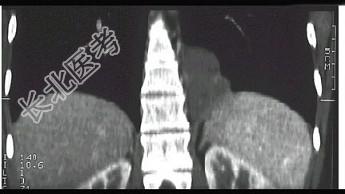

- 单项选择题男,18岁, 无明显症状, CT检查如图。最可能的诊断为 ( )

A、左下肺膈疝

B、左下肺肺隔离症

C、左下肺癌

D、神经纤维瘤

E、左下肺肺炎